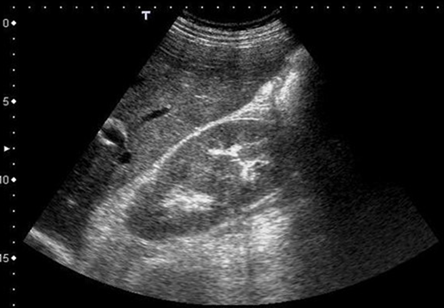

55 year old male , what is the abnormality seen on this scan ? us shows a column of Bertin in the right kidney as a normal variant. The ...

55 year old male , what is the abnormality seen on this scan ?image

us shows a column of Bertin in the right kidney as a normal variant.

The sonographic signs of hypertrophied columns of Bertin are characteristic. The only possible pitfall is the parapelvic cyst. Careful analysis of the echogenicity of such a cyst and its acoustic enhancement will help to differentiate it from hypertrophied columns of Bertin. The renal column (or Bertin column, or column of Bertin) is a medullary extension of the renal cortex in between the renal pyramids. It allows the cortex to be better anchored.